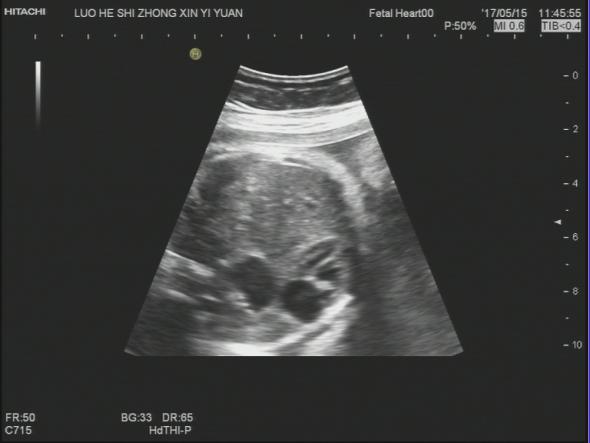

【声像图表现】 胎儿心脏:四腔心切面可显示,左心偏小,右心偏大.主动脉内径明显偏细,PA:7.1mm,PAV:84cm/s,AO:4.0mm,AOV:38cm/s,因体位限制,主动脉弓显示不清。胎儿腹部内脏:胆囊位于腹腔左侧,心脏及胃泡位于右侧胸腔,心房反位,心室左襻,肺动脉发自功能右室,主动脉发自功能左室,三尖瓣增厚,回声增强,四腔心切面可显示.左心明显偏小,右心明显扩大。因胎儿体积大位置较远,左房明显小,未探及明显的肺静脉血流信号入左房。

32周的孕妇,这次超声检查是发现胎儿肝脏,胆囊位于腹腔左侧,心脏及胃泡位于右侧胸腹腔,理论上胎儿肝脏、胆囊应位于腹腔右侧,胃泡位于腹腔左侧,心脏位于胸腔偏左侧,但是这个胎儿不仅存在着脏器反位,而且从声像图来看胃泡和心脏位于一个切面,难以分清是在胸腔还是腹腔。根据超声资料,胎儿心脏还表现左心偏小,右心偏大.主动脉内径明显偏细,因体位限制,主动脉弓显示不清。因胎儿体积大位置较远,左房明显小,未探及明显的肺静脉血流信号入左房,说明胎儿心脏也存在发育不良。